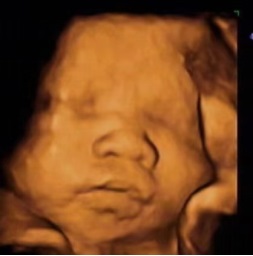

接着,就是我们孕期中最最重要的一次产科检查(22~24周)—中孕期系统性畸形筛查

此次为III级产科超声检查,俗称“大排畸”,为整个孕期最重要的一次超声检查,超声医师会按一定顺序对胎儿各个器官进行系统的筛查,可以排除胎儿大部分结构畸形。在检查过程中,如果胎儿配合,位置合适我们会留取一张胎儿颜面部的三维立体图像,并打印在报告中,给准妈妈和准爸爸看看宝宝在肚子里面的样子。

唇腭裂的宝宝 正常的宝宝